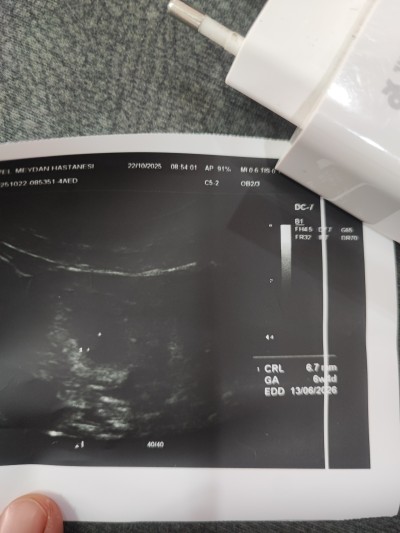

7 haftalık kalp atış 160 dedi doktor bebek kesenin altına doğru yapışık iki defa gidiyorum net görüntü vermiyor cinsiyet tahmini yapabilir misiniz

Gebelik haftası 7